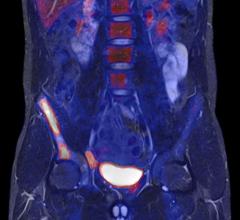

August 21, 2015 — A molecular imaging biomarker is able to detect fast-growing primary prostate cancer and distinguish ...